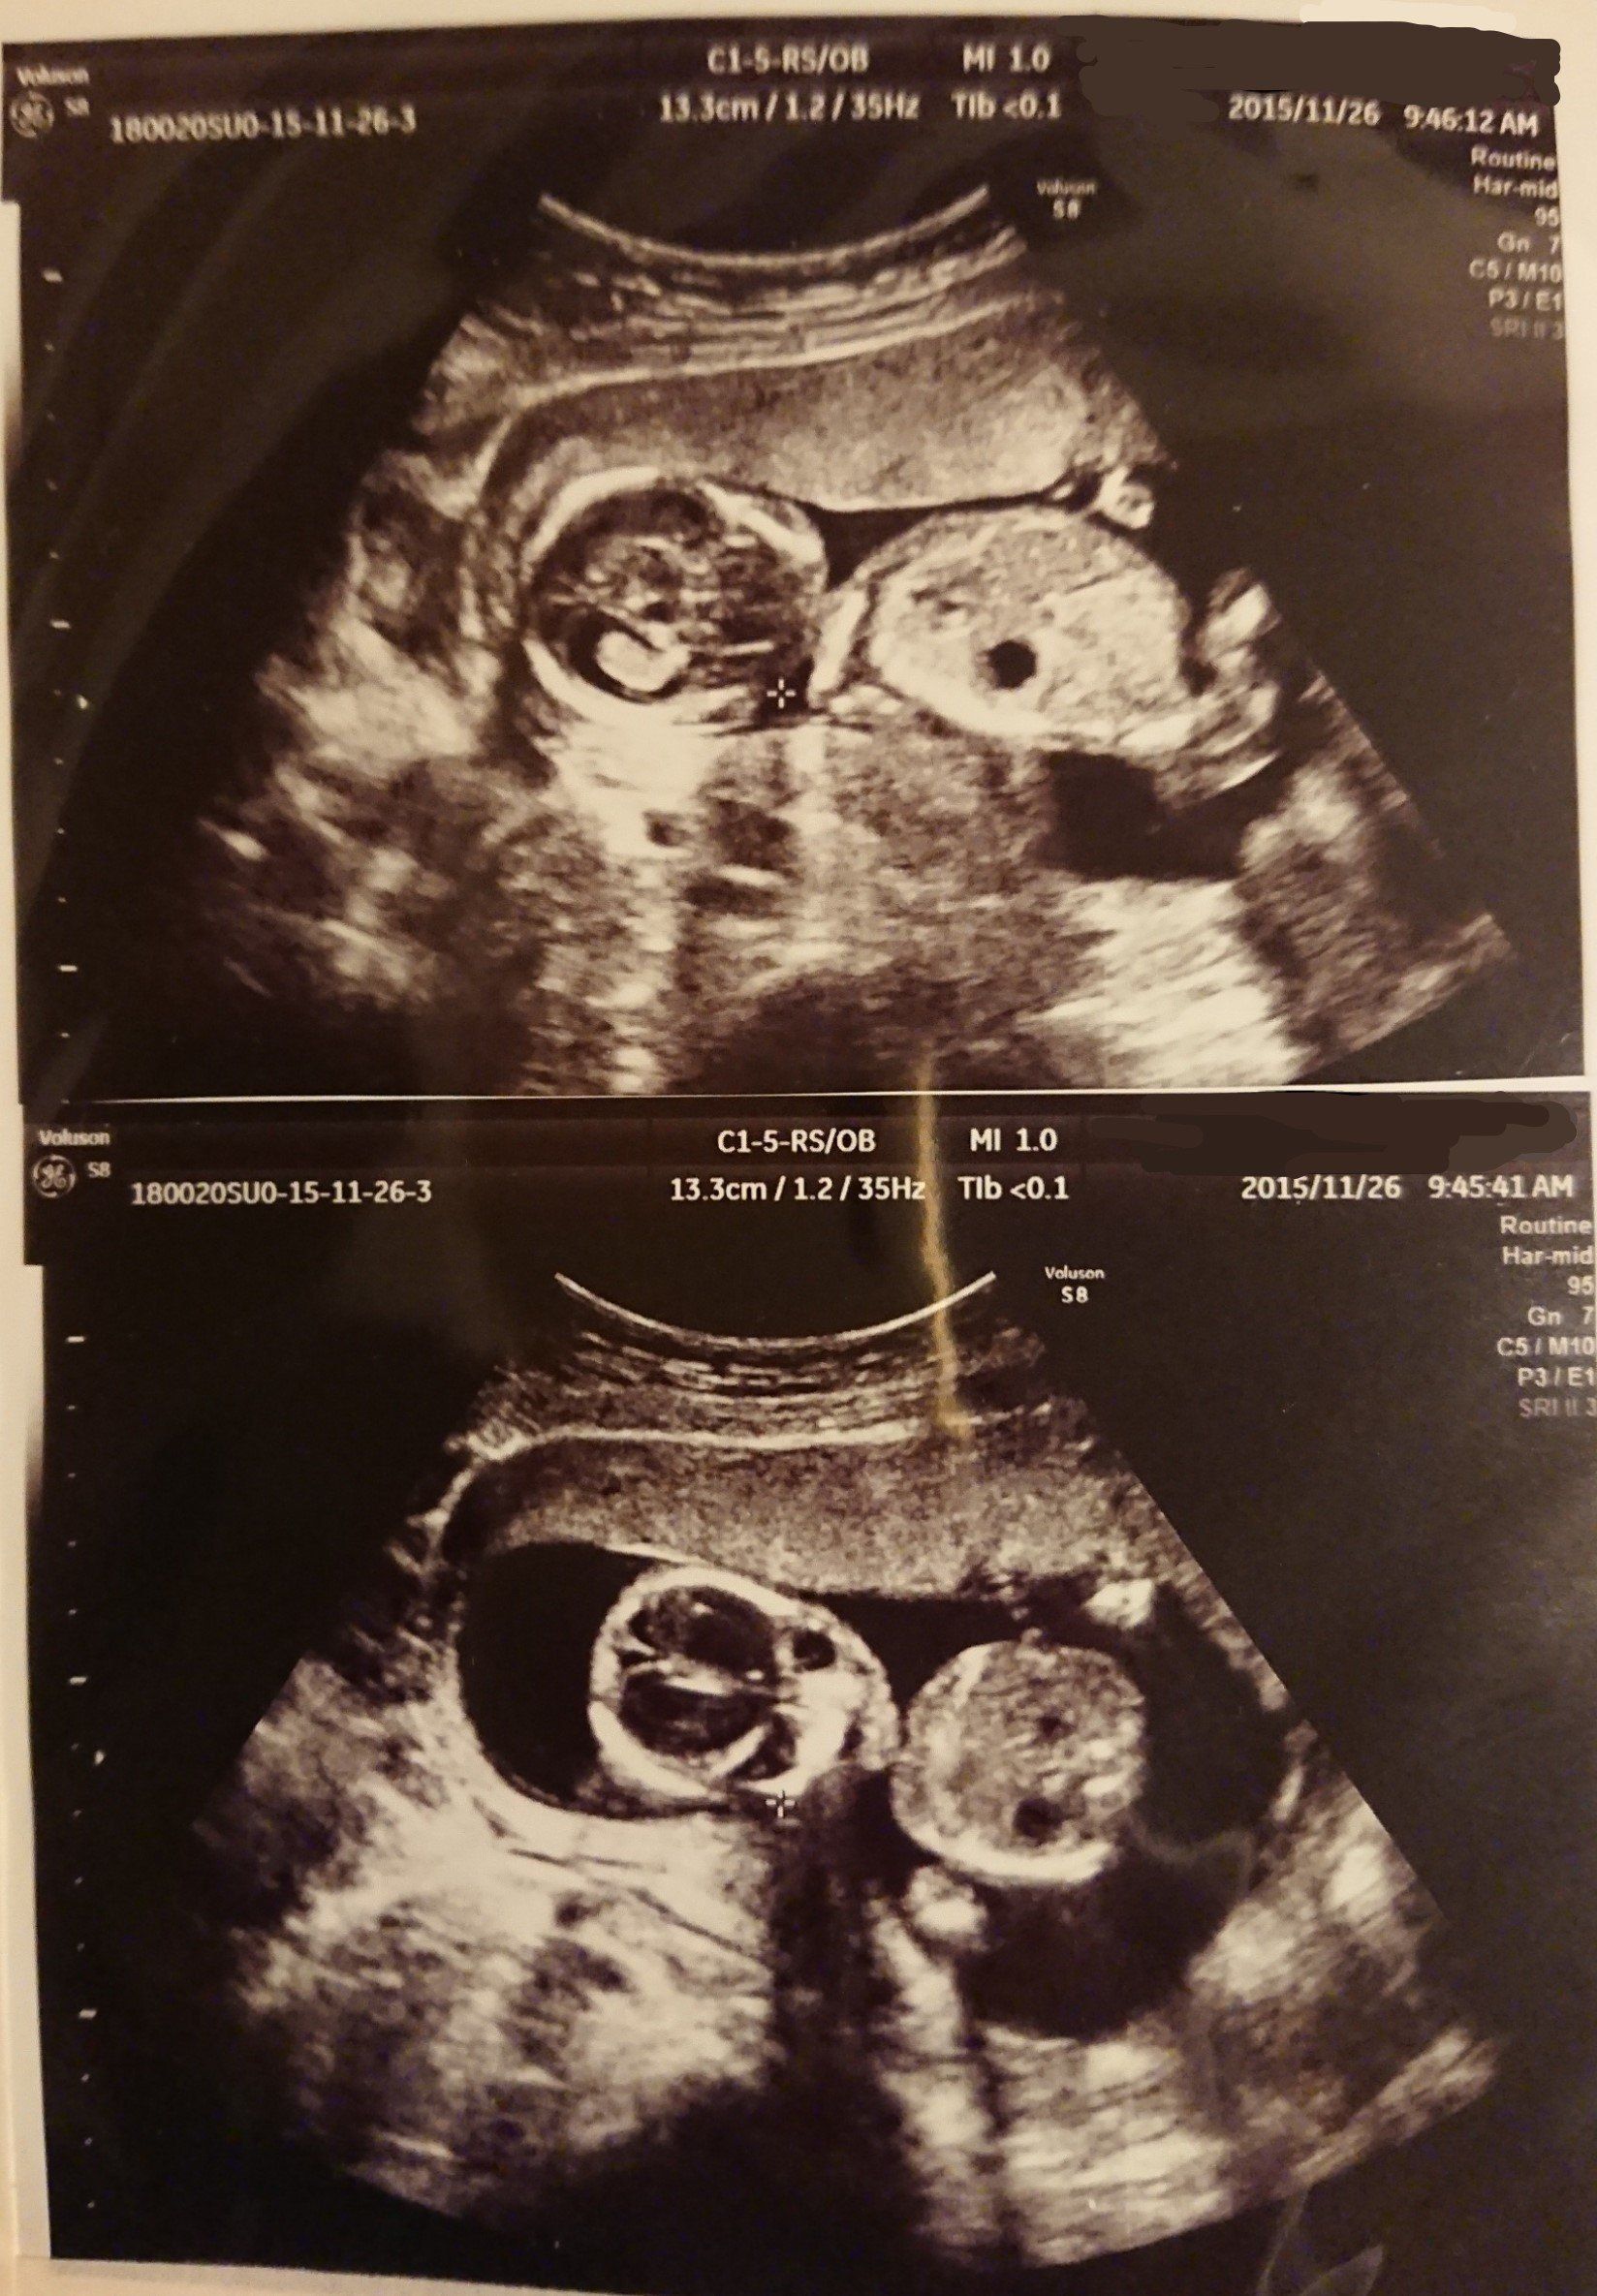

妊娠11週目 1カ月ぶりの健診。エコーを見てびっくり!

頭や手足などがはっきり見えて人間らしくなっていました。この時初めて「かわいい!」と思い、ママになることを実感したように思います。つわりはひどく仕事以外はソファーで横になっている状態。料理も匂いで気持ち悪くなるので作れず、野菜ジュースやゼリーを口にするのが精一杯でした。夫には外食やお弁当などで済ませてもらっていました。

おなかが大きくなり胃を圧迫しているのか、思うように食べられなくなってきました。常に苦しくなんだかムカムカするので、つらかったつわりの時期がまた来たような感じです。この日の健診では赤ちゃんがまばたきをするのが見られました。